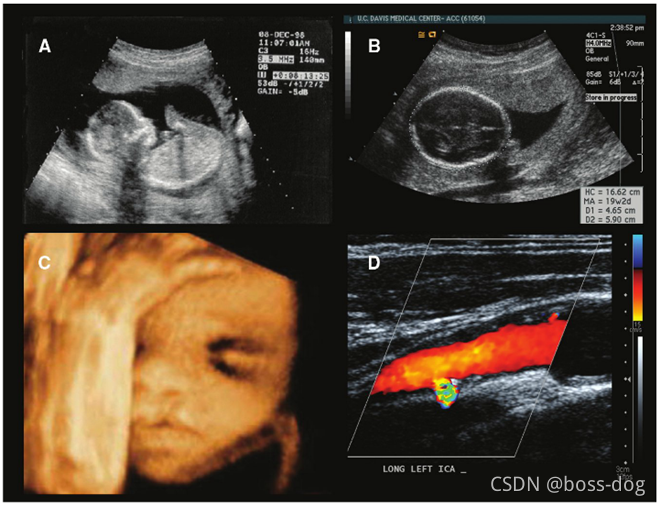

2.超声成像(UltraSound imaging)。没有那些辐射而且用的是声波,只不过频率要比声波要高,所以是安全的且特别方便,应用领域如解剖成像(Anatomical imaging)、多普勒超声(Doppler flow imaging,可以测量血管里面血流的速度和方向)、胎儿成像(Fetal Ultrasound)、心脏的超声成像(Echocardiography)。

Ultrasound imaging(超声成像)

A:胎儿超声图像

B:胎儿头部直径测量

C:通过多个二维图片,可以进行三维成像建模

D:血管成像多普勒超声成像,红颜色、蓝颜色、绿颜色都反映出这个血流得方向和大小